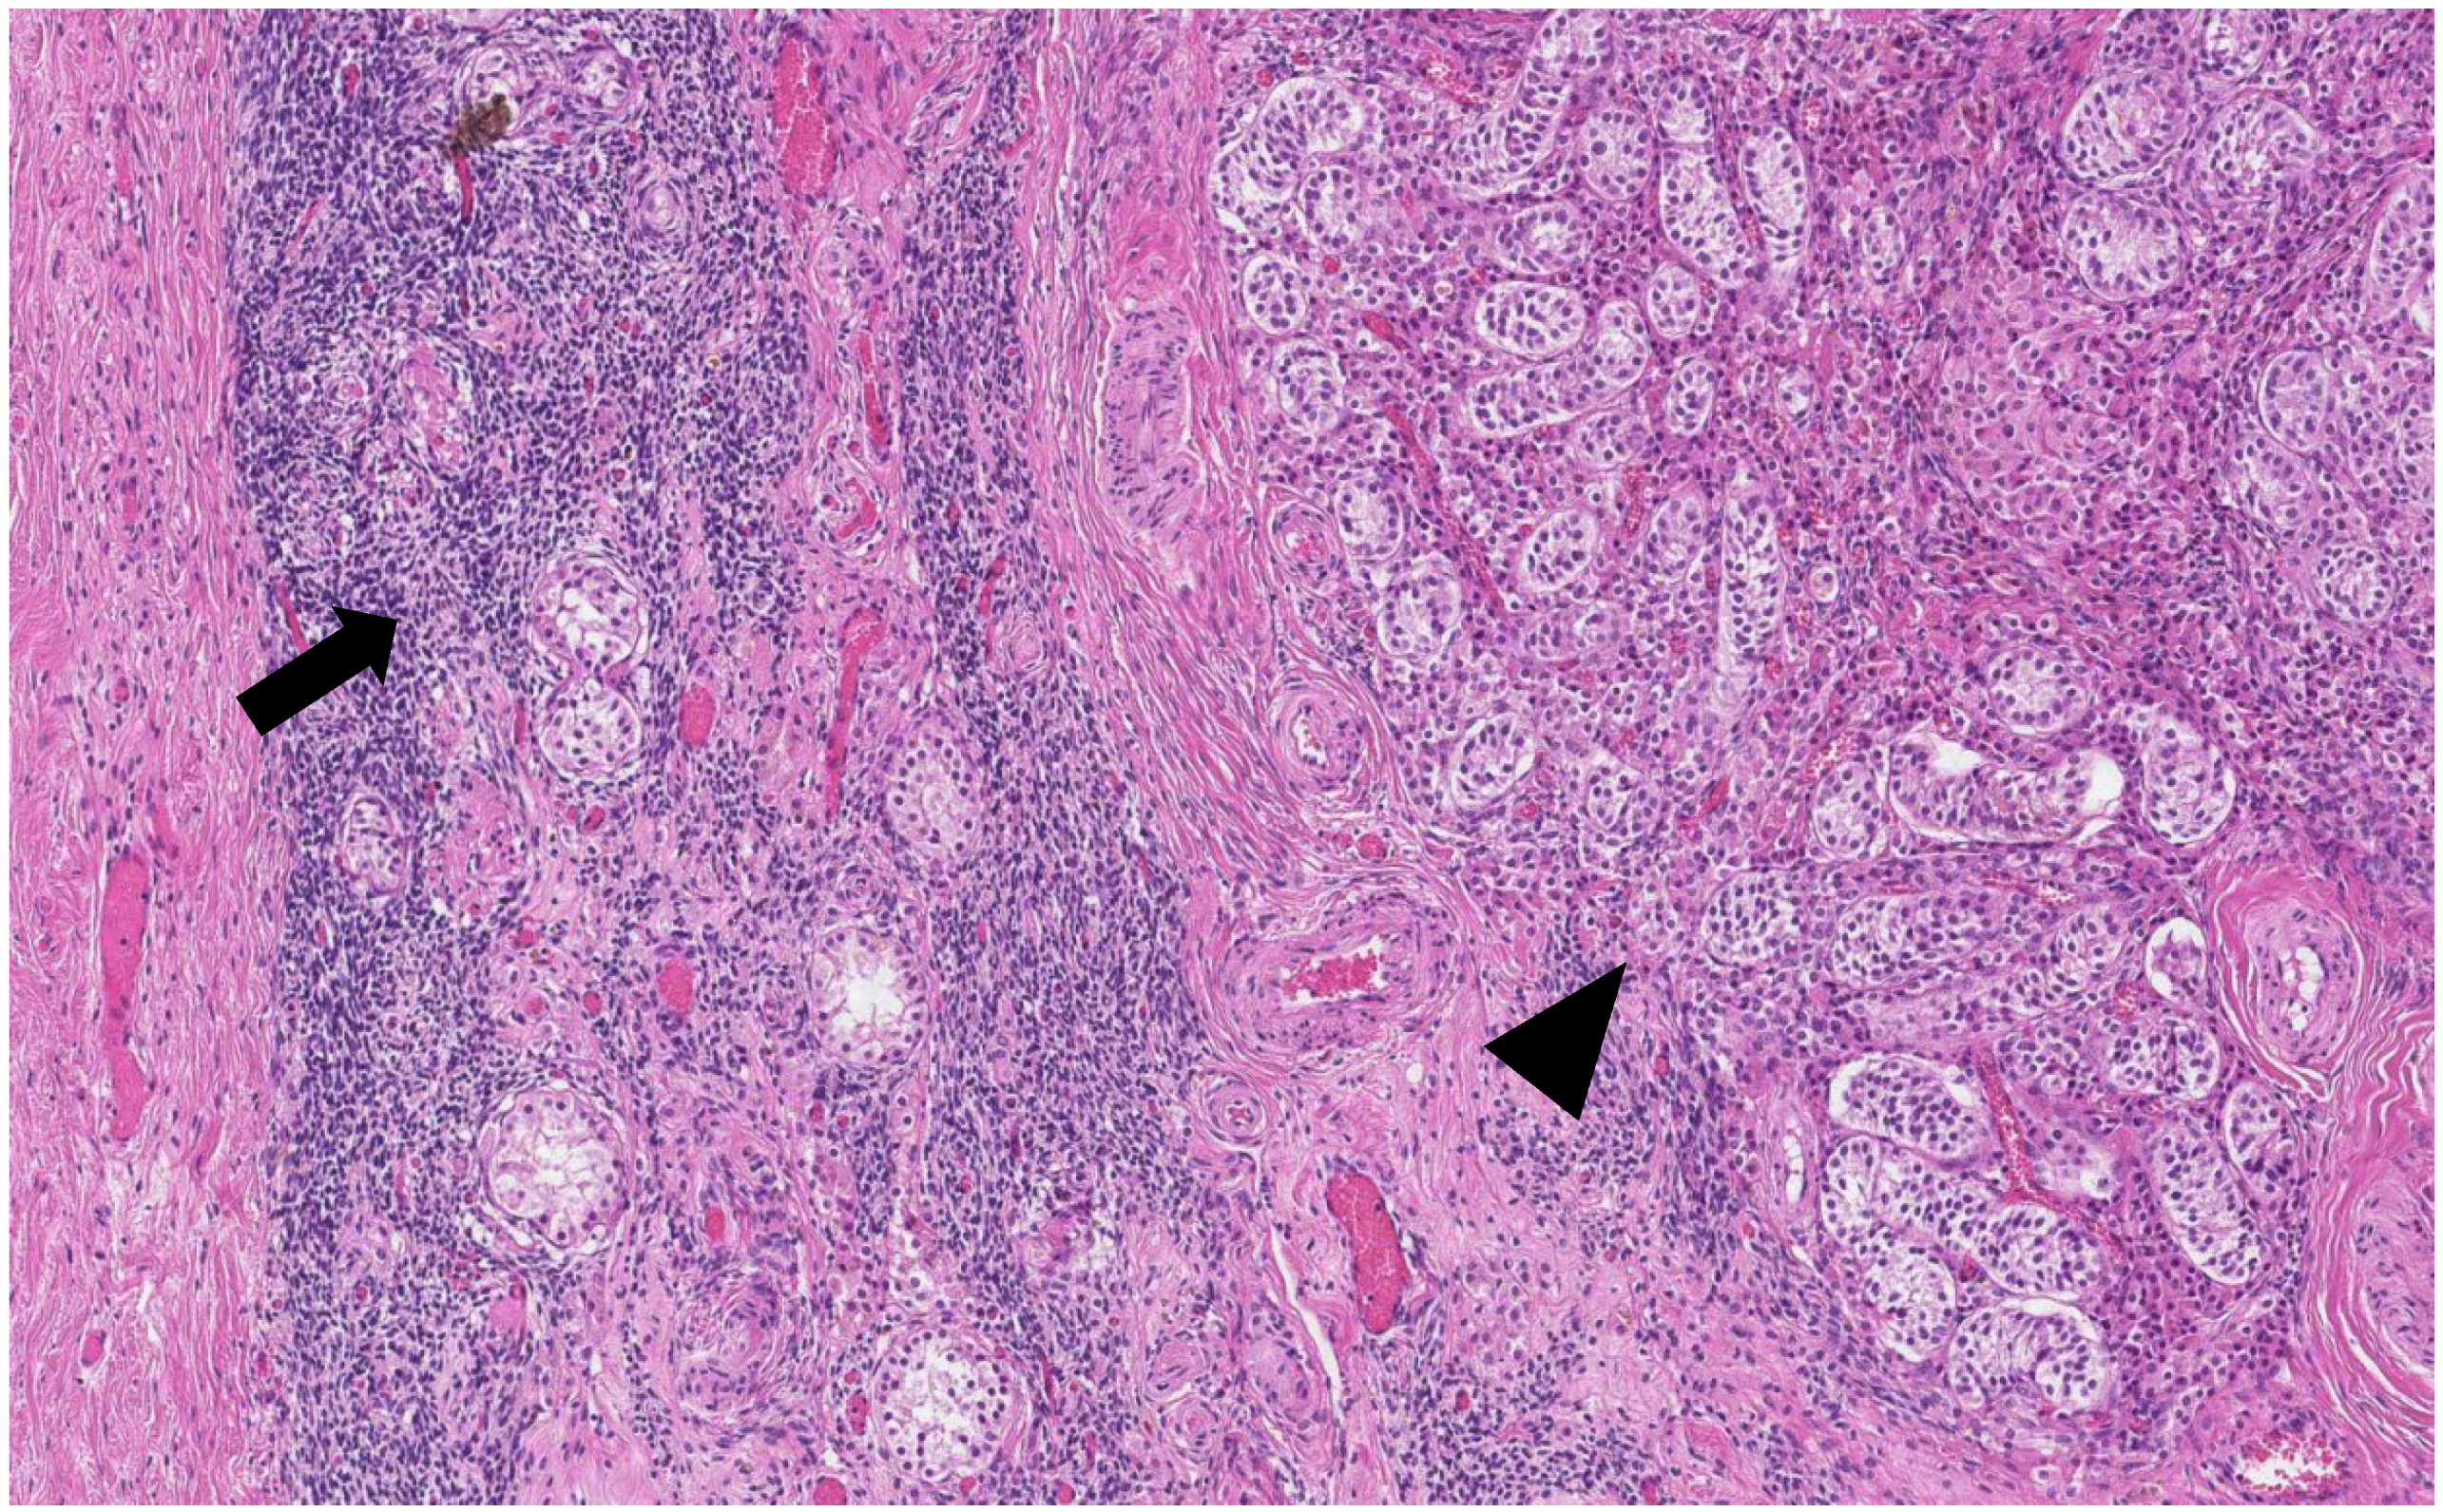

The histological analysis of the patient’s removed gonads revealed that there were hypoplastic testicles, which is a clinical sign of androgen insensitivity syndrome (Figure 3, Figure 4, Figure 5 and Figure 6). After the operation, testosterone analysis was repeated-hormone level significantly decreased to 0.83 nmol/L, which is a normal female-range value for a woman at that age.

Figure 4. Ovarian-type stroma (arrow) and tubules composed of immature Sertoli cells separated by Leydig cells (arrowhead) (H&E staining, ×50).